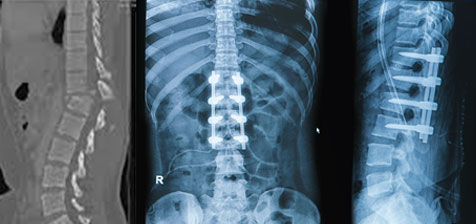

• Spinal fusion: Joining 2 vertebra with bone graft.